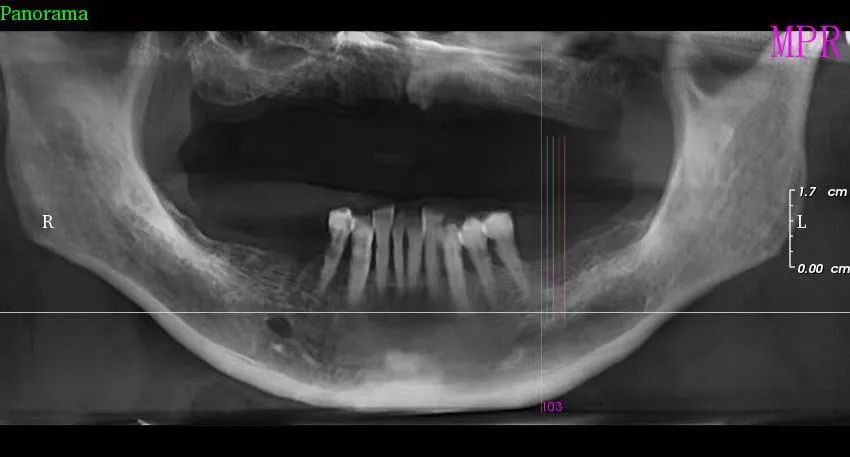

三、种植牙技术

目前,社会上很多人被牙齿缺失所困扰,牙齿缺失不但影响人的咀嚼和语言功能,对于人的面部美观也是一种影响,甚至有些人因缺失牙齿而不愿意张口说话,种植牙被誉为人类“第三副牙齿”,因其舒适、美观、功能好而被缺牙患者追捧。经卫建委批准,我院于2023年3月18日正式开展种植牙技术,开展当天门诊手术7例共计14颗植体,术后1天回访患者表示无红肿、无疼痛症状,术后7天回访一切良好无异常,术后10天拆线创口愈合良好,自开展口腔种植手术以来,有许多患者纷纷到科里进行相关咨询和检查,更是不断有患者预约意向种植,我院严格按照江西省医疗保障局、江西省卫生健康委员会关于公布实施口腔种植类医疗服务价格有关事项的通知—赣医保字《2023》3号文件执行操作,在手术诊疗中,严格操作流程,减少感染风险。我院口腔种植技术的成功和发展,不仅完善了传统牙齿修复技术的不足,而且在功能与美观上给了人们崭新的体验,我院致力于提供一站式口腔种植诊疗服务,必将为本县及周边缺失牙患者找回美丽、自信的微笑。

种植前 种植后

案例二